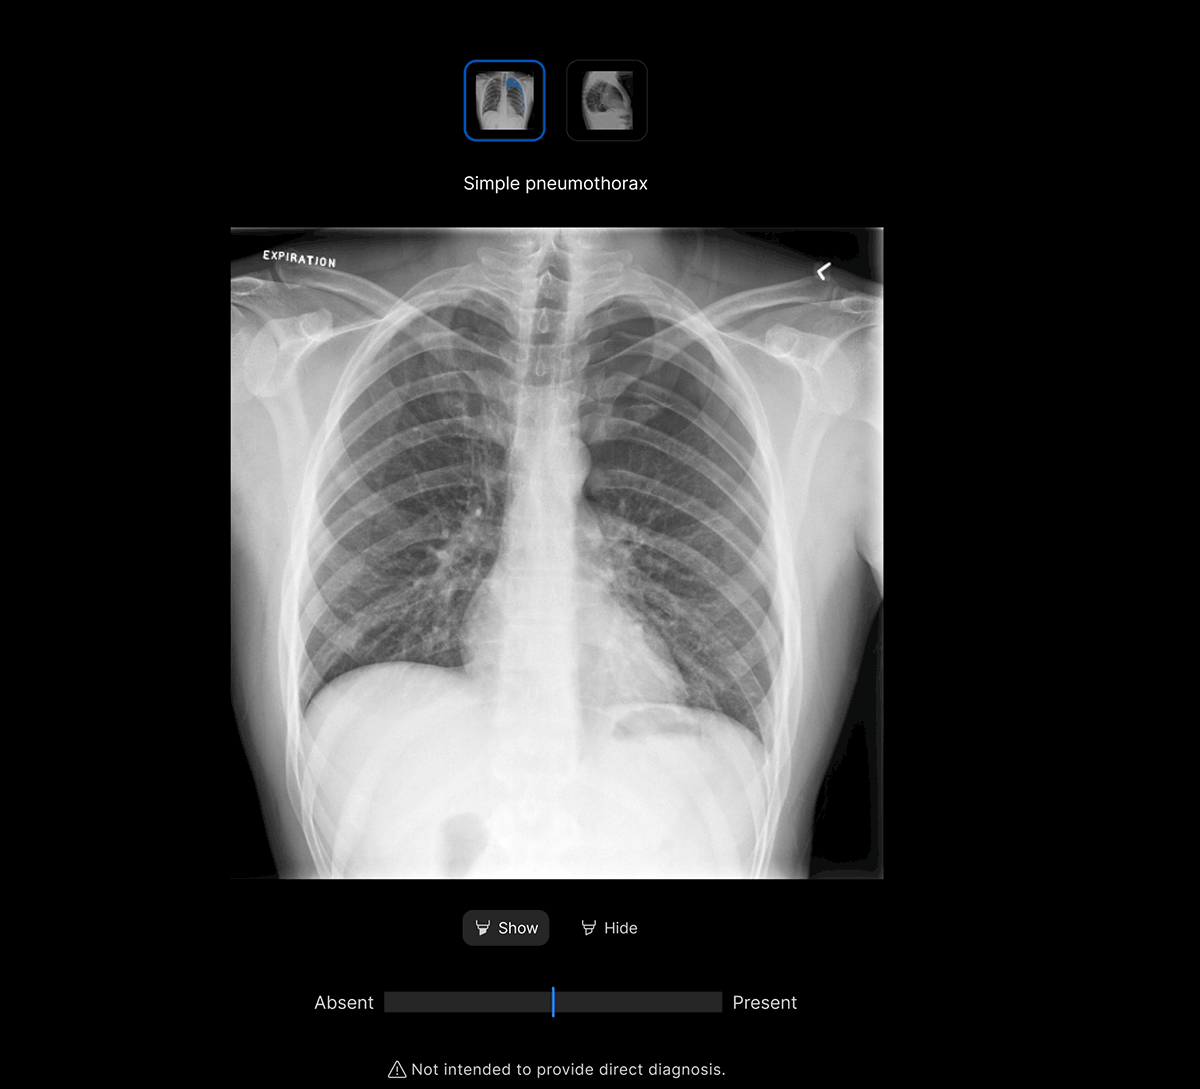

Intuitive UI. Powerful AI.

Designed by radiologists.

Designed to reduce cognitive load.

Seamless workflow.

The UI integrates seamlessly with PACS/ RIS, displaying a resizable, no-click overlay window with findings and localisation.

Customisable features.

Customisable thresholds for individual findings (to optimise for sensitivity / specificity), to tailor the workflow to your clinical setting or population.